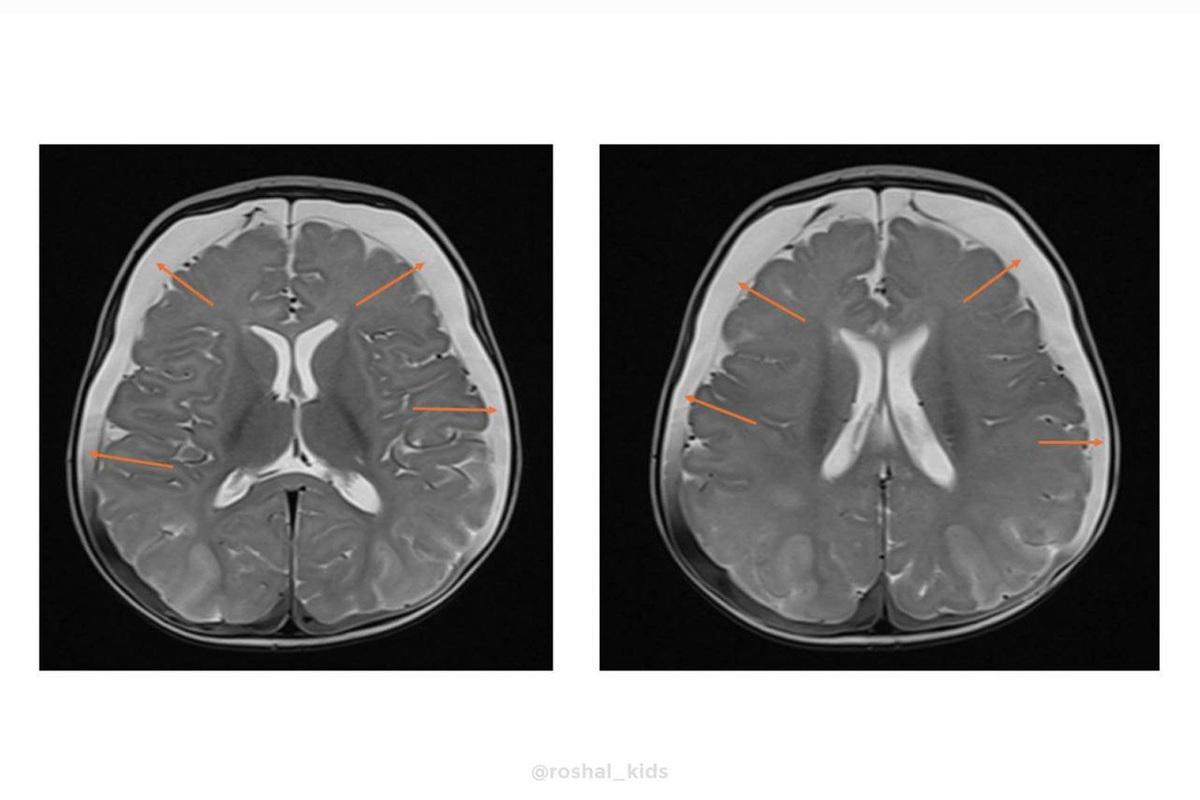

Как узнал «МК», в медучреждение в тяжелом состоянии привезли четырехмесячную девочку. У ребенка случился судорожный приступ. Обследование выявило пугающие симптомы: выпирающий родничок, увеличенный размер головы и критически высокий, почти в пять раз выше нормы, уровень аммиака в крови (194 мкмоль/л при норме до 47). Врачи выяснили, что у маленькой пациентки оказалось крайне редкое генетическое заболевание: ННН-синдром. Это нарушение цикла мочевины, врожденный сбой в обмене веществ. Организм не может перерабатывать белок, из-за этого происходит отравление аммиаком, буквально разрушающее мозг.

Специалисты подобрали терапию, которая помогла прекратить поступление белка. Это позволило предотвратить необратимое повреждение мозга. Уже через 24 часа уровень аммиака снизился до нормальных значений.